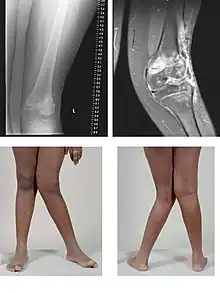

| Valgus deformity of the knee (genu valgum), seen in MRI and photograph | |

A valgus deformity is a condition in which the bone segment distal to a joint is angled outward, that is, angled laterally, away from the body's midline.[1] The opposite deformation, where the twist or angulation is directed medially, toward the center of the body, is called varus.

- Knee: genu valgum (from Latin genu = knee) – the tibia is turned outward in relation to the femur, resulting in a knock-kneed appearance. Common causes of valgus knee (colloquially "knock-knee") in adults include arthritis of the knee and traumatic injuries.